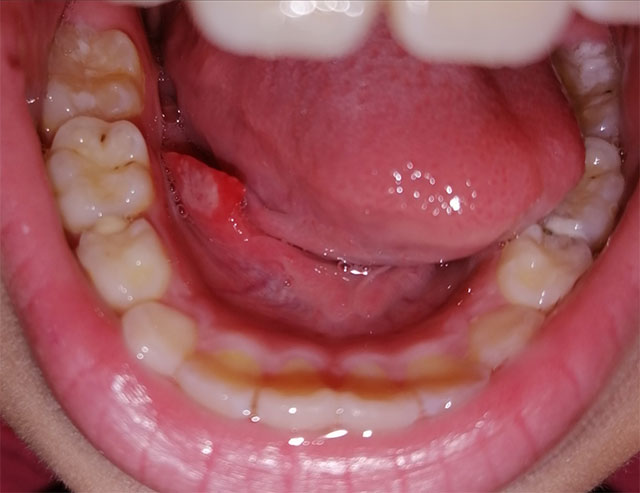

心急!請問這是口腔癌症狀嗎?!

你所形容的情況更加像是痱滋,和周圍腫起了的肉塊。這個年紀口腔癌的機會非常罕有!若果過幾天還沒有好轉,請帶他去看醫生,因為口述的病徵不是最好的診斷方法。